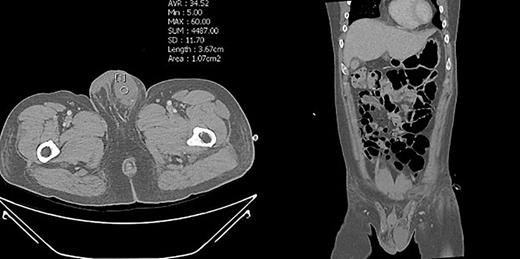

To prevent the patient from further self-injury, simple therapeutic restraint of both arms was performed with the patient’s consent, and sedative medication was administered. He was closely observed in the intensive care unit to monitor his hemoglobin and systemic conditions. Additional transfusion treatment was provided as needed. Psychiatric medicines including antipsychotics and sedatives (Clozapine 125–250 mg/day, haloperidol 2.5–5 mg, and lorazepam 1–2 mg/day) were prescribed by a psychiatrist. After 5 days of taking the psychiatric medication, the patient no longer reported the impulse to harm himself, and was able to release the simple restraint on both arms. No further self-harm occurred until he was discharged, presumably due to the proper effects of taking psychiatric medication. Anticoagulant agents (5 mg apixaban, twice per day), subcutaneous heparin injection (5,000 IU, twice per day), and alprostadil (10 mg, once per day) were given for circulation to prevent the thrombosis of vessels. On POD2 from the first operation, a testicular scan with technetium pertechnetate revealed the viability of the remnant left testis compared with the amputated right testis (Fig. 7). On POD4, contrast-enhanced CT showed the enhancement of the vessel into the testis (Fig. 8). On POD7, scrotum Doppler ultrasonography revealed the Doppler signal in the parenchyma of the testis (Fig. 9). Testosterone levels increased after the surgeries and normalized on POD5 (Fig. 10). He was discharged on POD9 without any skin complication (Fig. 6c). After discharge, he returned to our clinic for follow-up on POD13 and 23. On the visit, laboratory follow-up including testosterone and free testosterone was checked and confirmed as normal (Fig. 10).

Enhanced abdominal pelvis CT of the patient. The left testis of the left scrotum revealed patent with showing vascularity.

We performed five examinations to check the viability of the replanted testis. First, in the operating room, we used indocyanine green after replantation (Fig. 4). Indocyanine green fluorescence perfusion showed testicular perfusion, which enabled the immediate checking of the viability of vessels. This procedure is appropriate for checking the viability of microscopic vessels that may be damaged during a milking test. Second, a testicular scan showed the viability of the testis (Fig. 7). One testis is markedly different from the lesion of orchiectomy. However, the scan resolution was low because of a wide range of arterial courses and the disturbance of the urethral catheter or bladder. Third, contrast-enhanced CT displayed the vascularity of the testis and the surrounding parts (Fig. 8). However, the shooting time to the enhanced phase could affect the failure of the vascularity of the testis. No protocol for this case has been established in our institute; therefore, CT was a nonspecific tool for testicular examination. Fourth, ultrasonography efficiently showed the vascularity inside the testis (Fig. 9). However, skin wound could inhibit or limit ultrasonography. Fifth, we indirectly checked the testicular function based on testosterone levels (Fig. 10). A laboratory examination should be performed continuously. However, this procedure could be limited among hypogonadal men, and the separate testicular function of each testis could not be easily identified. Nevertheless, these techniques will help determine the viability of the testis in specific situations.